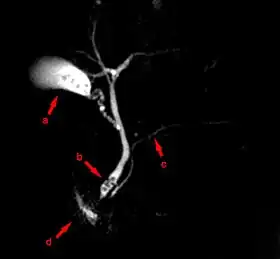

![]() MRCP image showing stones in the distal common bile duct: (a) Gallbladder with stones, (b) Stones in bile duct, (c) Pancreatic duct, (d) Duodenum. | |

Magnetic resonance cholangiopancreatography (MRCP) is a medical imaging technique. It uses magnetic resonance imaging to visualize the biliary and pancreatic ducts non-invasively. This procedure can be used to determine whether gallstones are lodged in any of the ducts surrounding the gallbladder.